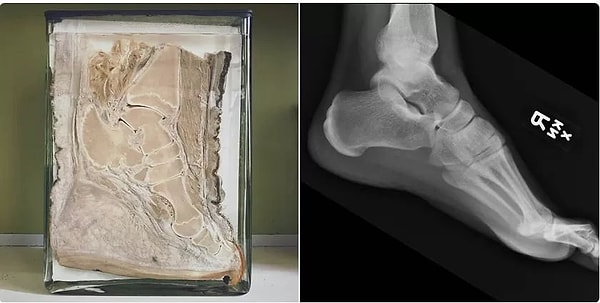

11. Кости в стопе слона выглядят как кости в стопе человека.